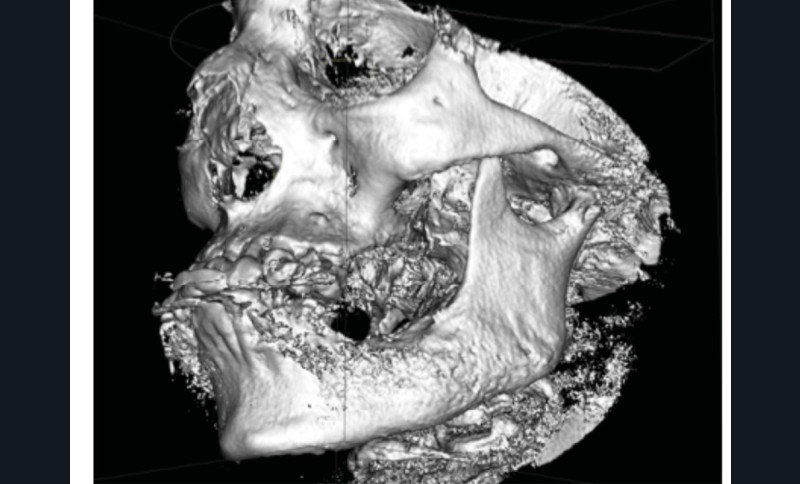

L’examen radiologique (scanner ou tomographie a faisceau conique) est très évocateur. Il montre un épaississement périosté avec « aspect mixte » de l’os médullaire et des « perforations corticales ».

L’ostéomyélite passe par plusieurs stades au cours de son évolution. Au début, les zones d’ostéolyse et de sclérose sont invisibles radiologiquement…